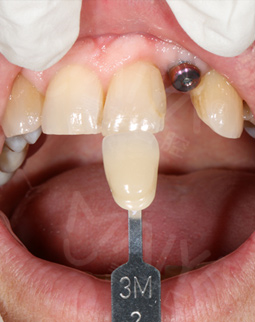

今天又来复诊,愈合基台无松动,可以戴牙冠了,取模也很方便,然后还有比色,一颗种植牙看着只是种牙而已,其实每个环节还是挺细心的,这次复诊刚好碰上活动,在此祝福生日快乐,也希望更多的缺牙人能在这里重拾口福健康!